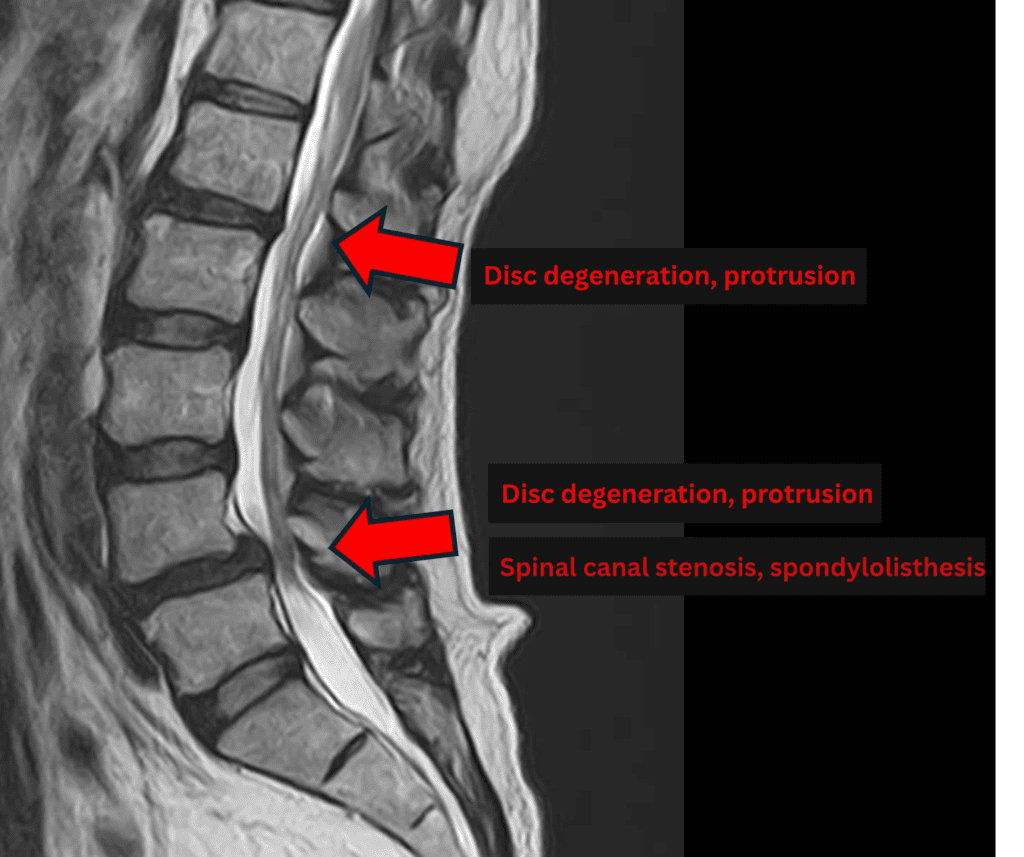

Imaging and findings

- L1/2: Disc degeneration, disc bulging, foraminal stenosis

- L2/3, L3/4, L5/S1: Mild disc degeneration, mild bulging, mild foraminal stenosis

- L4/5: Disc degeneration, disc bulging, foraminal stenosis, spinal canal stenosis, mild anterior degenerative spondylolisthesis

The above findings were also observed on the imaging.

Based on these findings, compression of the spinal canal due to disc pathology at L1/2 and L4/5 was considered the most likely cause of the patient’s symptoms.